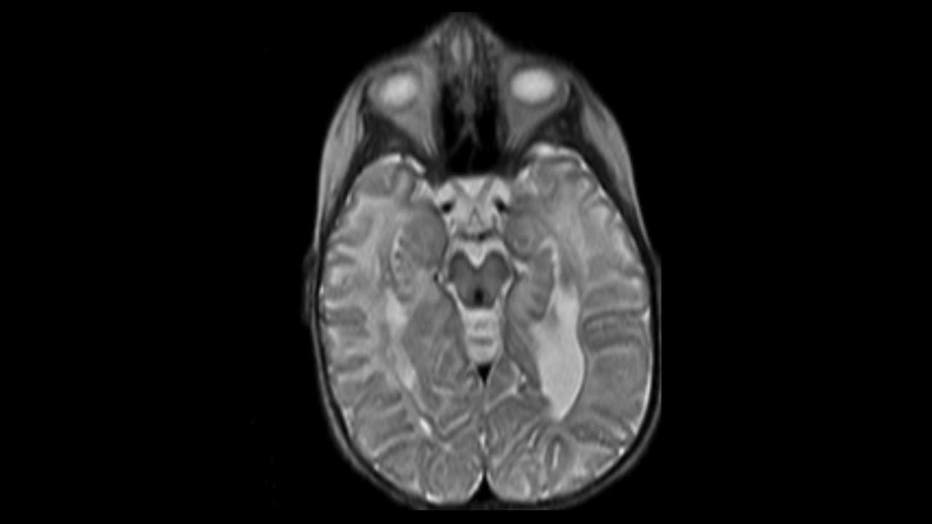

When Ashtyn Fellenz was just 3 years old, she underwent groundbreaking gene therapy. That helped her survive a deadly childhood disease into her 20s.

When Fellenz died, her parents agreed to donate her brain for scientific research.

In December 2024, Children's Wisconsin performed the autopsy, preserving Ashtyn's brain in hemispheres. But somewhere along the way, Children's Wisconsin admitted it accidentally threw half of her brain away.

Dr. Paola Leone said it was the most important half for research.

"It’s irreplaceable, irreplaceable," said Dr. Paola Leone, Rowan University.